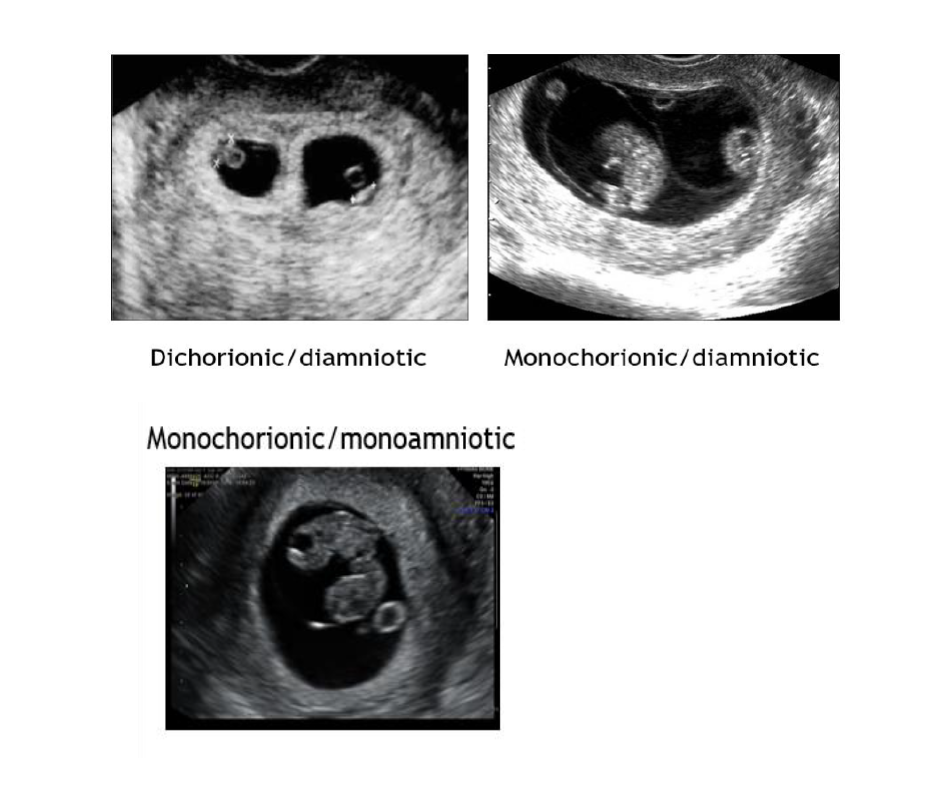

Conversely, monozygotic twinning occurs when there is the typical release of a singular oocyte from the dominant follicle and fertilization occurs. It is followed by division of the resulting zygote. The timing of the division dictates the type of twinning that occurs. Monozygotic twinning will result in a dichorionic-diamniotic twin pair when the division occurs day 0-3. A monochorionic-diamniotic twin pair occurs when the division occurs between day 3 and 8. Division between days 8 and 13 generates a monochorionic-monoamniotic twin pregnancy. Conjoined twins consequently results when division process begins after day 13 [16].

Several guiding principles are used to define chorionicity including membrane thickness, number of membrane layers, number of placental sites, presence of the lambda or T-sign, and other composite measures; (Figure 2) and (Figure 3). Composite measures would include ability to discern the number of placental masses, number of gestational sacs, number of fetal poles, and whether fetal sex is concordant/discordant. The number of yolk sacs usually equates to the number of amnions. Membrane thickness in monochorionic (MC) pairs has been described subjectively as “thin” or “whispy”; this description has been investigated using numerical measurement with thresholds for thickness ranging from <1.0-2.0 mm [18-20].

Figure 2. First trimester ultrasound and chorionicity/amnionicity.